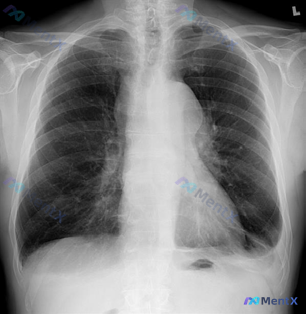

整理到一张儿科胸部正位X线片的资料,先不说是最终结论,看看大家的第一眼思路会不会有不同。 基本情况 - 人群:婴幼儿(从投照判断) - 投照体位:仰卧位(AP位) 主要影像表现 1. 肺野:右肺上野可见斑片状、云絮状高密度影,边界模糊 2. 肺纹理:双肺门区域纹理略显增粗、模糊,以右肺中上野及双肺内...